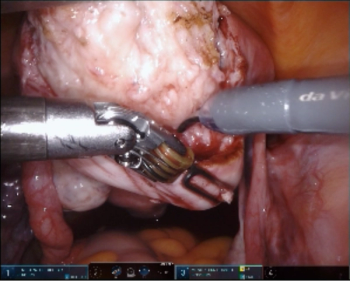

Chronic pain appears to play a major role in the relationship between endometriosis and depression, according to a recent meta-analysis.

New research compared the effectiveness of MRI and TVS for detecting rectosigmoid endometriosis.